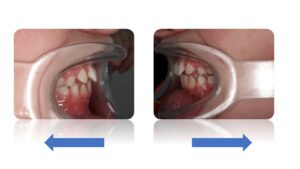

La Classe II Subdivision

La classes II subdivision fonctionnelle est la conséquence d’une mastication préférentielle voir exclusivement unilatérale. Cette dysfonction engendre alors une bascule du plan d’occlusion dans le plan frontal mais également dans le plan vertical et sagittal.

L’orthodontie systémique permet d’appréhender cette pathologie par l’analyse des latéralités mandibulaires (AFMP).

Le traitement qui en découle est donc fonctionnel et stable car il permet une réorientation du plan occlusal, symétrisant ainsi les AFMP et donc la mastication.

C’est donc la fonction qui joue le rôle de contention des traitements systémiques.